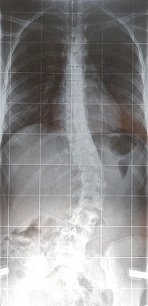

Da ich mir eure eingestellten Bilder immer so gern anschaue, will ich jetzt auch mal ein paar Bilder von mir zeigen.

Ich fange mal an mit dem 1. Rö-bild, was am 20.11.08 bei Dr. Hoffmann gemacht wurde. Nur zur Erinnerung: th.17° und lu 39° n. Cobb

- 20.11.08.JPG (27.06 KiB) 18318 mal betrachtet